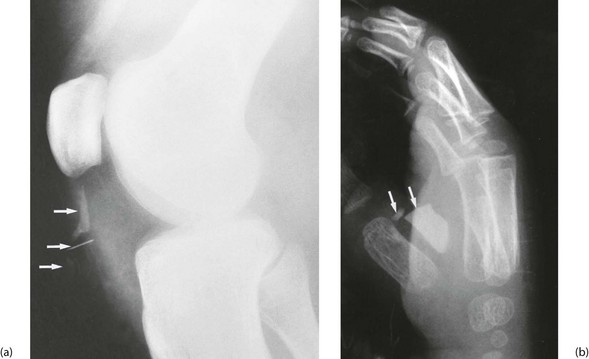

Foreign bodies: The history of the injury can indicate the likelihood of foreign bodies being retained in the wound. The main types are agricultural and road dirt, wood splinters, and glass and metal fragments. Plain radiology reveals metal and usually glass (see Fig. 17.1) but a negative X-ray does not exclude its presence. Remember that a foreign body unrecognised at the time may result in litigation later.